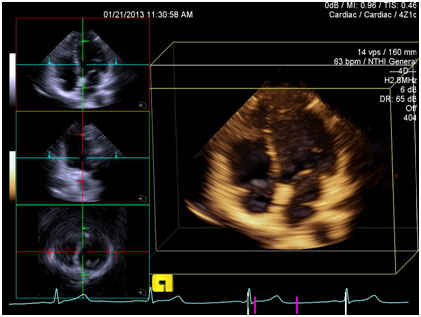

Volume cardiac image with multiplanar reformatting

Volume cardiac image with multiplanar reformatting.

Accurate assessment of dynamic heart function is a critical need. Real-time 3D ultrasound imaging of the heart (4D) requires processing at least 100 megasamples per second with minimal latency, which is a big challenge

Collecting all of the information needed for an ultrasound exam in a single heartbeat without stitching together data from multiple heartbeats enables better quality imaging and speeds up example time. This is especially true in many disease states with irregular heartbeats and also enables real time interventional guidance and automatic measurements.

GPU computing enables us to apply signal processing algorithms to dramatically improve real-time ultrasound imaging of the heart.